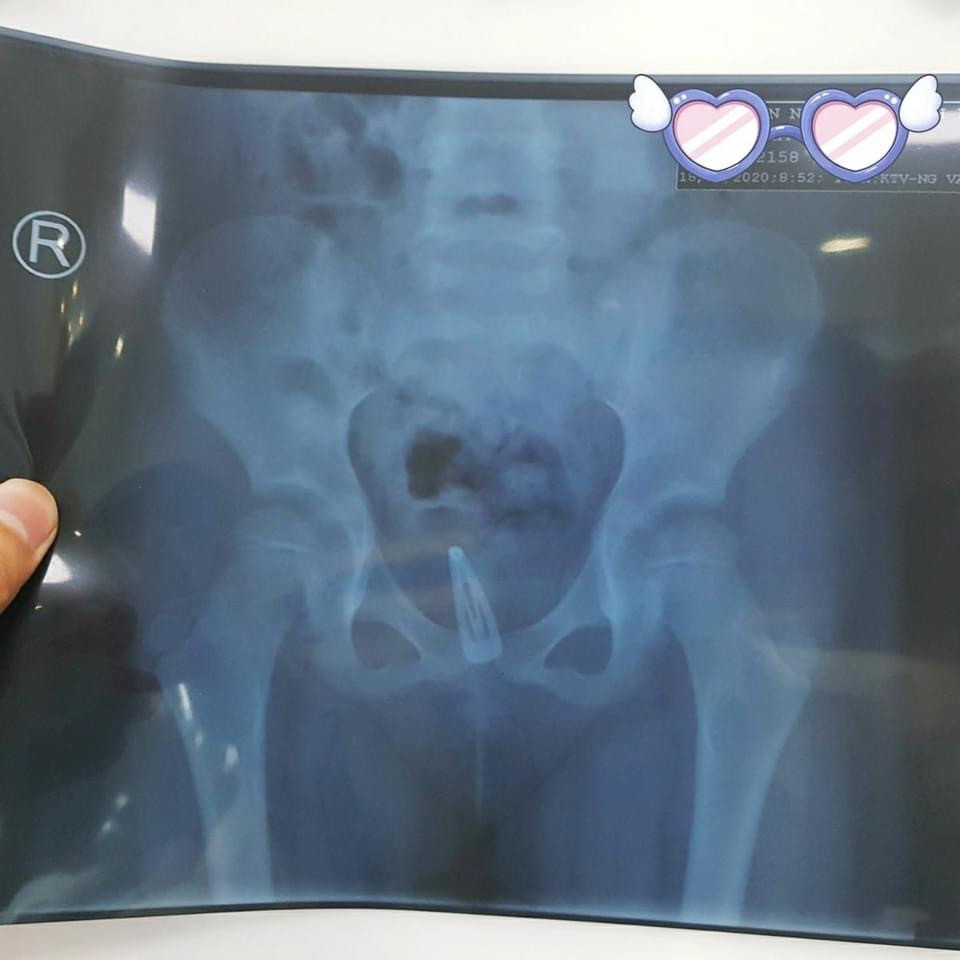

Kẹp tóc mắc kẹt trong cái âm đạo của bé gái suốt 3 tháng ảnh 1  Hình siêu âm phát hiện dị vật (ảnh:BVCC)

Tại BV, bé đc chụp X Quang bụng không sửa soạn, thử nước tiểu, siêu âm bụng... Bé được chẩn đoán nhiễm trùng tiểu -  dị vật âm đạo.